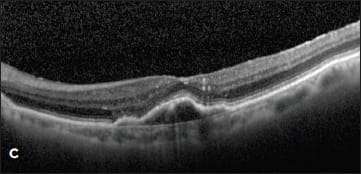

Figure 2. A new occult CNV with PED (A). After treatment with bevacizumab, OCT showed persistent subretinal fluid (B). The therapy was switched to ranibizumab, and after nine injections, the PED had slightly grown in size, but the subretinal fluid had resolved (C). Due to PED growth, the patient was switched to aflibercept, and after two injections, the subretinal fluid resolved, and the PED flattened (D).

Case 2. The second case involved a 99-year-old woman who presented with a new occult lesion in the left eye. There was loss of one line of vision at 20/40, and a new PED with associated subretinal fluid was noted on her OCT (Figure 2A). She was treated with three doses of monthly bevacizumab with a minimal response, and her vision declined to 20/50+2 (Figure 2B).

She was then switched to monthly ranibizumab. The subretinal fluid resolved with one injection, and her vision improved to 20/30. However, after nine injections of monthly ranibizumab, her vision declined to 20/40, with a small amount of intraretinal fluid and an enlarging PED (Figure 2C). This visit coincided with the commercially availability of aflibercept, and the treatment was changed to monthly 2.0 mg aflibercept. After two injections, her vision improved to 20/30, the PED flattened, and the subretinal fluid resolved (Figure 2D).